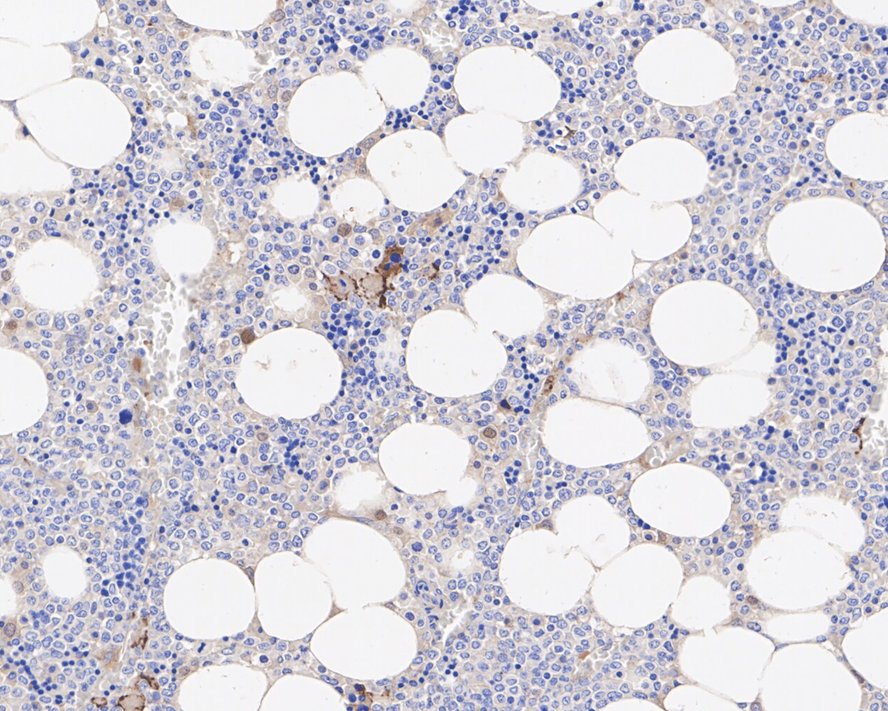

Catalog# EM1902-15

CD42b Mouse Monoclonal Antibody [13G2]

IHC-P

FC

Human

unconjugated